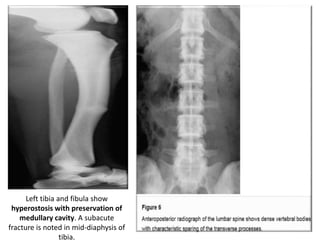

• Radiographically, there is generalized osteosclerosis similar

to osteopetrosis, but with preservation of the medullary

canal of long bones.

• Dense vertebral bodies with characteristic

sparing of the transverse processes is seen.

• Because the medullary cavities are preserved, patients

with pyknodysostosis (unlike patients with

osteopetrosis) tend not to have concurrent anemia.

• On the other hand, as with osteopetrosis, the bones

are brittle and prone to recurrent fractures.

Left tibia and fibula show

hyperostosis with preservation of

medullary cavity. A subacute

fracture is noted in mid-diaphysis of

tibia.